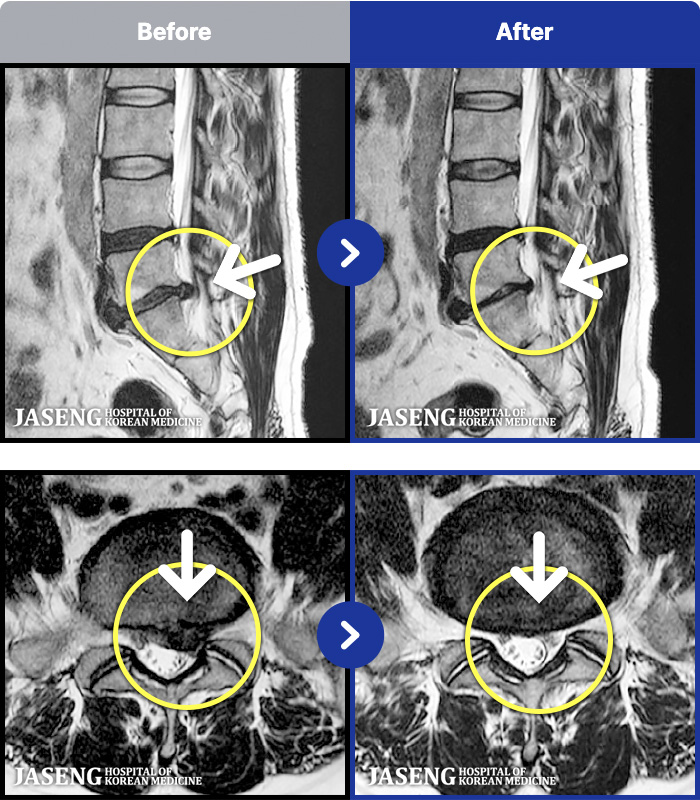

[] 23.11.11~25.06.04

ȯںп Ǹ ǿ ԿǾ, ο ġ ۿ Ƿ ġḦ Ͻñ ٶϴ.